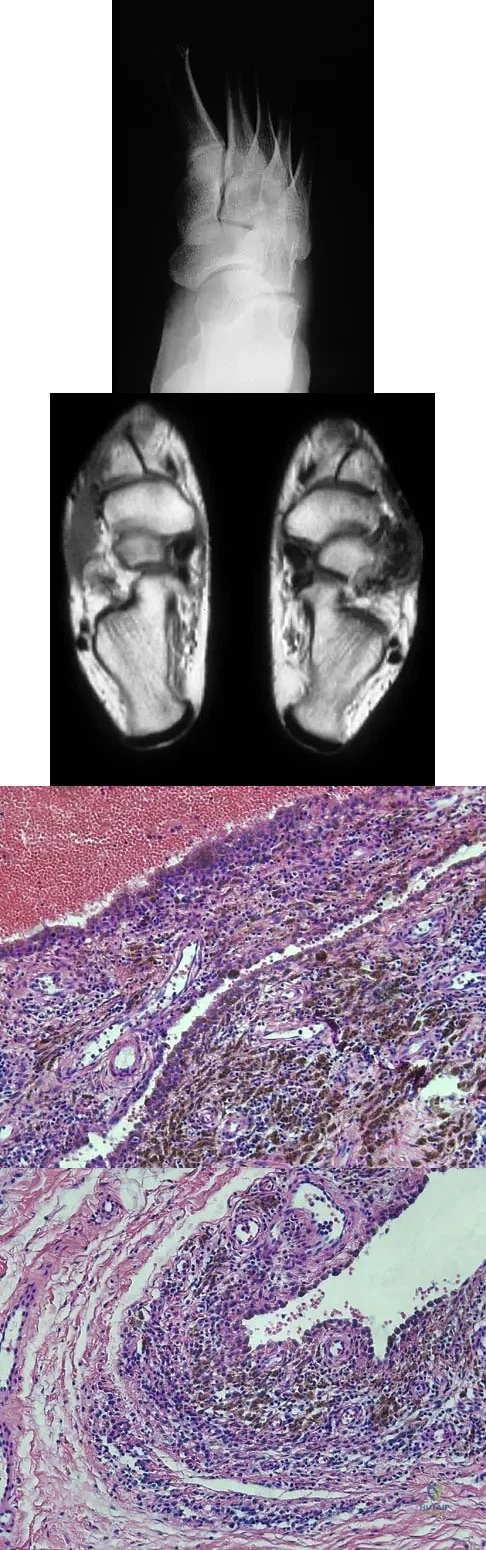

A 16-year-old girl has a painful foot mass. A radiograph, MRI scan, and biopsy specimens are shown in Figures 35a through 35d. What is the most likely diagnosis?

Explanation